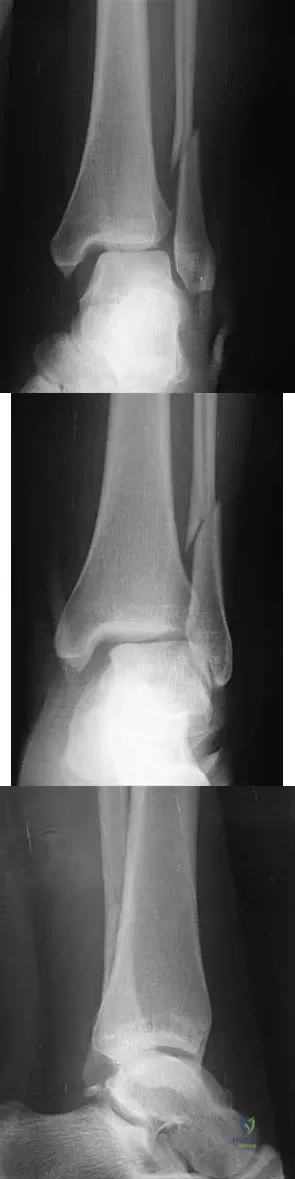

A 25-year-old woman has significant pain and swelling in her left ankle after falling off her bicycle. Examination reveals that she is neurovascularly intact. Radiographs are shown in Figures 33a through 33c. What is the next most appropriate step in management?